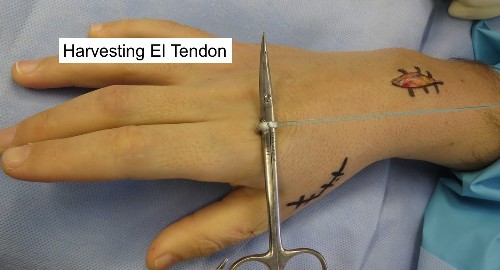

2. EI to EPL tendon transfer.

- There are 2 tendons that extend the Index finger ( EI & EDC tendons)

- The EI tendon is available for transfer because the EDC tendon to the index finger can still provide normal index finger extension on its own

- The Extensor Indicis (EI) tendon (used to extend the index finger) is redirected to take over the function of the EPL.